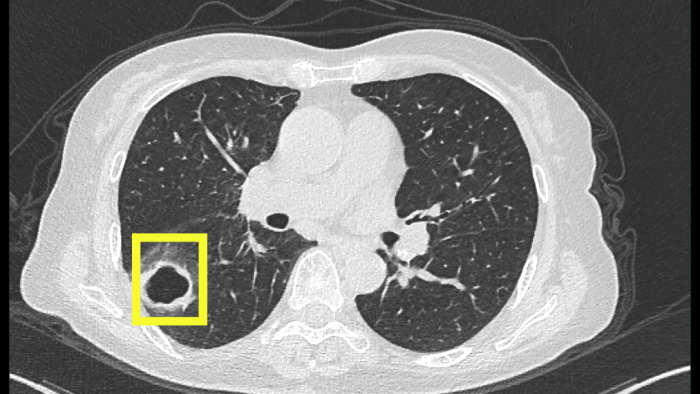

最開(kāi)始以為只是普通感冒,但柴阿姨自行吃藥后并沒(méi)有好轉(zhuǎn)。感到焦慮的柴阿姨便到當(dāng)?shù)蒯t(yī)院就診,經(jīng)肺部CT檢查發(fā)現(xiàn),肺部出現(xiàn)空洞病灶。

迷團(tuán)終于解開(kāi),原來(lái)引起柴阿姨肺部空洞的“罪魁禍?zhǔn)住辈皇欠谓Y(jié)核,而是真菌感染。

該患者是以咳嗽伴肺部空洞性病灶來(lái)就診的,最常見(jiàn)的病因是結(jié)核分枝桿菌引起的肺結(jié)核,但做了結(jié)核的相關(guān)檢查均未提示肺結(jié)核。而當(dāng)常規(guī)的檢驗(yàn)技術(shù)未發(fā)現(xiàn)病原菌時(shí),氣管鏡檢查及肺泡灌洗液的宏基因組測(cè)序就非常重要,可以讓患者少走很多彎路,使診斷及時(shí)明確,讓患者得到精準(zhǔn)治療。